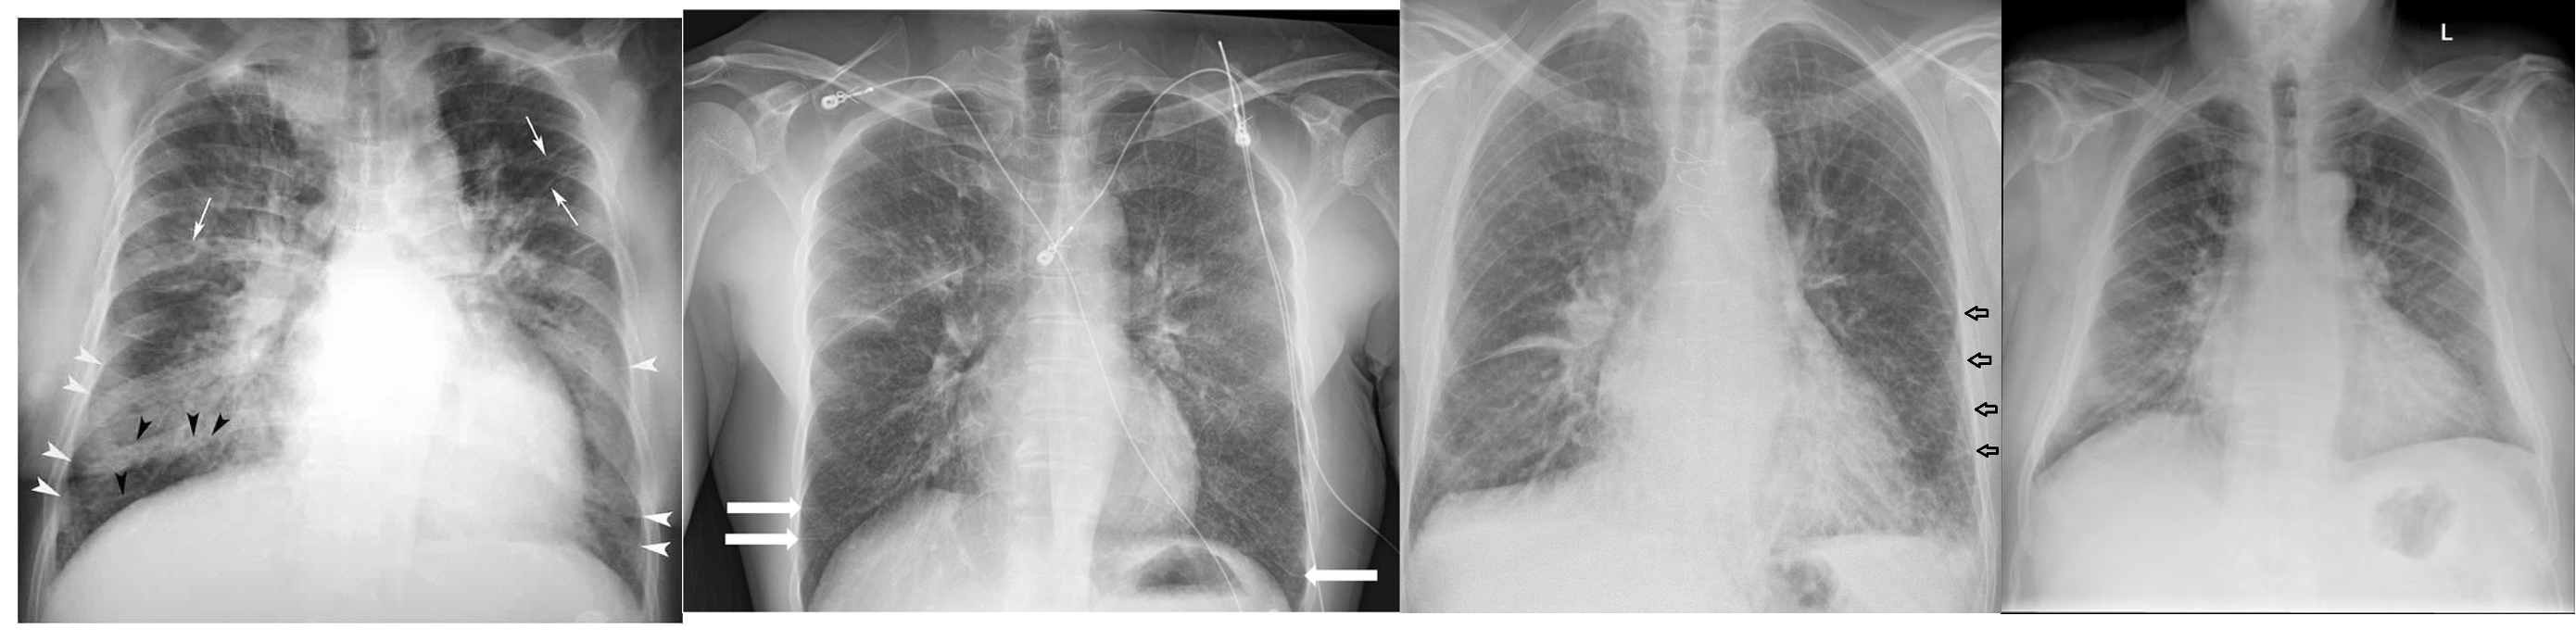

1) Chest X-ray:

- Cardiomegaly (not in diastolic failure)

- Pulmonary edema

- Pleural effusion

- Kerly B lines (interstitial edema)

(Image: Kerly B lines)

(Image: Cardiomegaly & pulmonary edema)

- Chest X ray:

- Cardiomegaly

Kerly B lines( interstitial edema)

Prominent blood vessels in upper lung field (called cephali sation)

How to calculate Cardiomegaly Horizontal diameter of the heart divided by widest horizontal distance in the chest cavity. If more than 0.5 ⇒ cardiomegaly (How to remember: heart/chest)

Kerley B Lines

Cardiomegaly & pulmonary edema